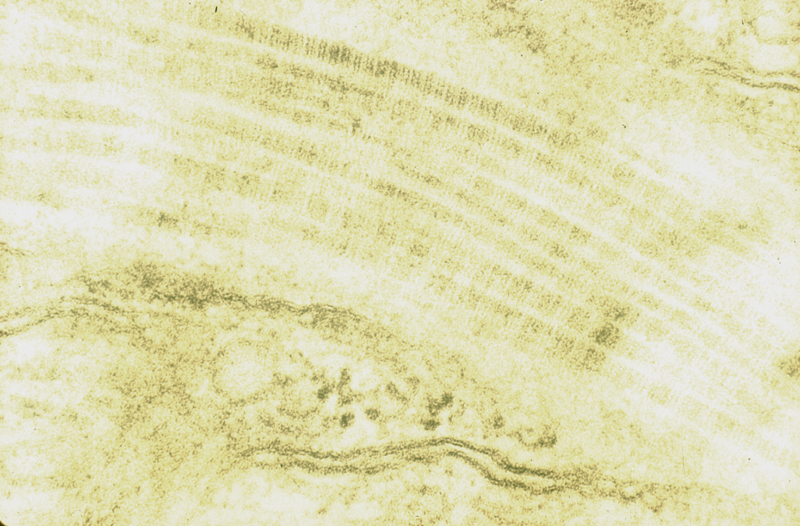

Síntesis del colágeno

colagenop.JPG (495073 bytes) Sintesis colageno01.JPG (32561 bytes) proteinas1.jpg (170414 bytes) proteinas2.jpg (226863 bytes)

Imágenes histológicas

cicatriz01p.JPG (321749 bytes) cicatriz02p.JPG (492337 bytes) cicatriz03p.JPG (236643 bytes)